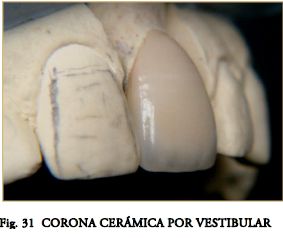

Hasta la aparición de los Postes Cerámicos, fabricados en base a Óx. de Circonio (ZrO), la posibilidad de lograr efectos ópticos similares a los dentarios era impensable. Los sistemas cerámicos no se han impuesto (entre otras causas) por presentar espesores poco conservadores y ser muy rígidos y estresantes con el riesgo de provocar fracturas radiculares intratables. Sin embargo los nuevos PPF conjugan excelentes propiedades estéticas con muy buenas propiedades mecánicas. Pueden ser “blanco opacos” para disminuir la sombra gris hacia la encía, o “blanco translúcidos” (Figs. 1, 2, 3, 5), para mantener la estética y permitir el pasaje de la luz de curado. Al eliminar la masa interna oscura de los postes metálicos se mejoran mucho las cualidades ópticas. Si bien en coronas metal-cerámica el efecto es inapreciable, es excelente en las cerámicas sin núcleo y para algunos autores también en algunas cerámicas de núcleo (In-Ceram).

- Cementado de la Corona con Cementos Convencionales (Fig.33), se pueden usar los resinosos recordando que el núcleo opaco impide el grabado con ácido Flúorhídrico (HF).